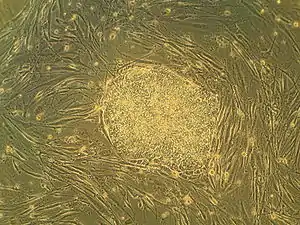

Embryonic stem cells (ESCs), derived from the blastocyst stage of early mammalian embryos, are distinguished by their ability to differentiate into any embryonic cell type and by their ability to self-renew. It is these traits that makes them valuable in the scientific and medical fields. ESCs have a normal karyotype, maintain high telomerase activity, and exhibit remarkable long-term proliferative potential.[6]

Embryonic stem cells of the inner cell mass are pluripotent, meaning they are able to differentiate to generate primitive ectoderm, which ultimately differentiates during gastrulation into all derivatives of the three primary germ layers: ectoderm, endoderm, and mesoderm. These germ layers generate each of the more than 220 cell types in the adult human body. When provided with the appropriate signals, ESCs initially form precursor cells that in subsequently differentiate into the desired cell types. Pluripotency distinguishes embryonic stem cells from adult stem cells, which are multipotent and can only produce a limited number of cell types.

Under defined conditions, embryonic stem cells are capable of self-renewing indefinitely in an undifferentiated state. Self-renewal conditions must prevent the cells from clumping and maintain an environment that supports an unspecialized state.[7] Typically this is done in the lab with media containing serum and leukemia inhibitory factor or serum-free media supplements with two inhibitory drugs ("2i"), the MEK inhibitor PD03259010 and GSK-3 inhibitor CHIR99021.[8]